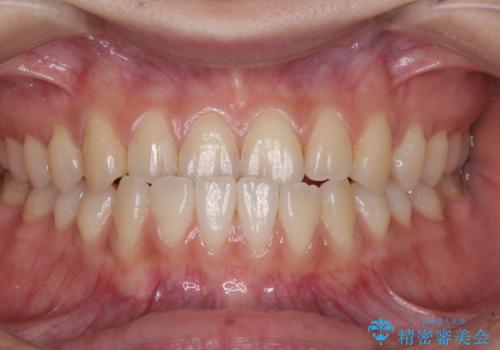

前歯のクロスバイトを治したい ワイヤー装置による矯正治療

- 前歯の反対咬合を気にして来院された患者様です。

クロスバイト改善まではスムーズに進みましたが、その後は強い舌の突出癖によりオープンバイトの期間が長く続きました。

舌のトレーニングをしっかりと実施してもらい、何とか仕上げることができました。